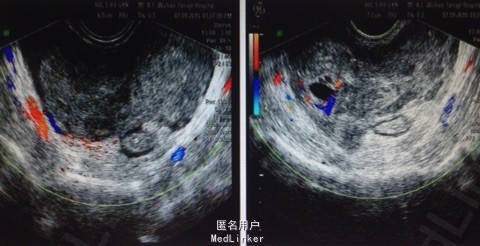

患者女,40岁,已婚。因"下腹胀痛不适2天"入院。 现病史:患者自诉前夜无明显诱因出现下腹不规则胀痛,能忍受,昨白天缓解,今上午再次出现腹胀不适,遂于普爱医院检查彩超示子宫后方非均质性回声块,盆腔积液,H-HCG(-),血常规未见异常。现为求进一步诊治,今来我院门诊,门诊以"腹痛待查黄体破裂?"收入院。 婚育史:23岁结婚,G7P2. 既往史:体健。有乙肝携带,2010年因不孕行腹腔镜探查术。

体格检查:T 36.7℃,P 90次/分,R 20次/分,BP 107/71mmHg. 门诊资料: 2015-09-07武汉市普爱医院检查彩超示子宫后方非均质性回声块(凝血块可能 建议结合临床),盆腔积液,肝胆脾彩超示盆腹腔积液,H-HCG(-),血常规未见异常。